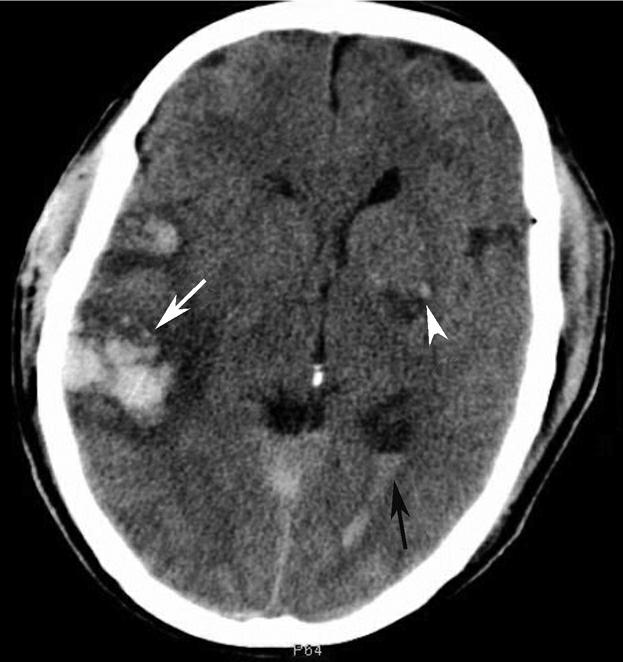

基底节为脑卒中的好发部位,与纹状动脉的解剖特点有关,深穿支动脉的破裂和栓塞可分别引起基底节区的出血和梗死(图1-2-32、图1-2-33)。

图1-2-32 脑出血

A.右侧壳核脑出血,形成高密度血肿(★);B.右侧丘脑出血,呈球形高密度影(箭)